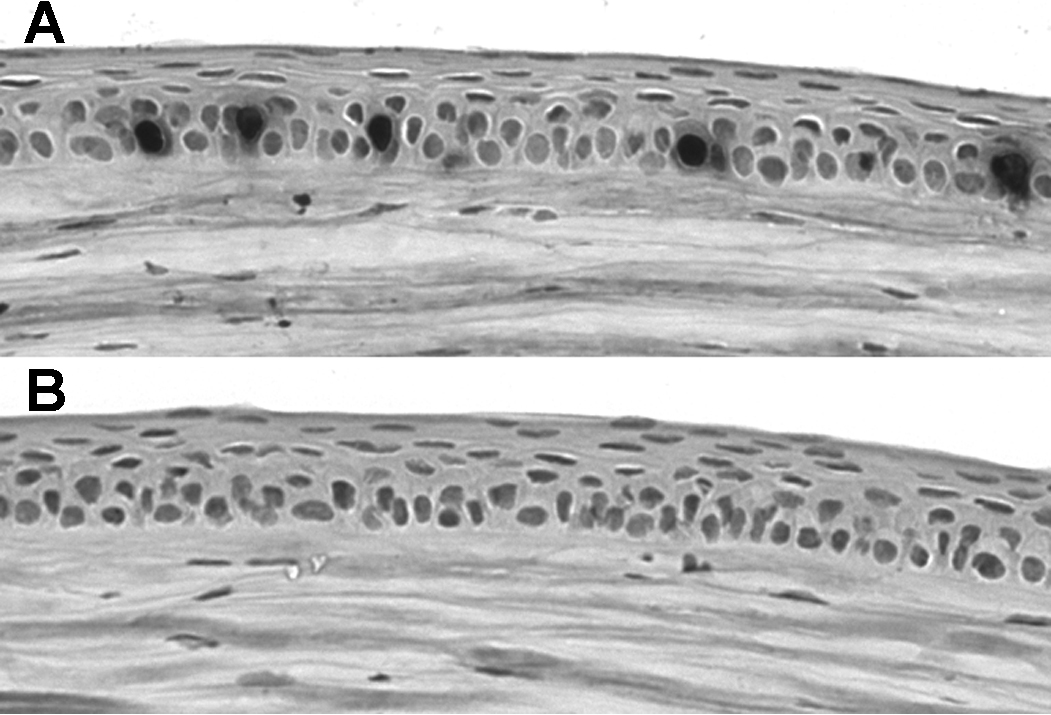

Figure 2. Cyclopamine completely inhibits corneal epithelial proliferation in vivo. A: Immunostaining of corneal epithelium 2 h after injection with BrdU in control mouse injected with vehicle only. Five BrdU-postive

nuclei are labeled. B: Immunostaining of corneal epithelium 2 h after injection with BrdU in mouse injected with 32 mg/kg cyclopamine. No BrdU-positive

nuclei are detectable, and no positive nuclei were detected in any section of the corneas of 3 cyclopamine-treated mice.